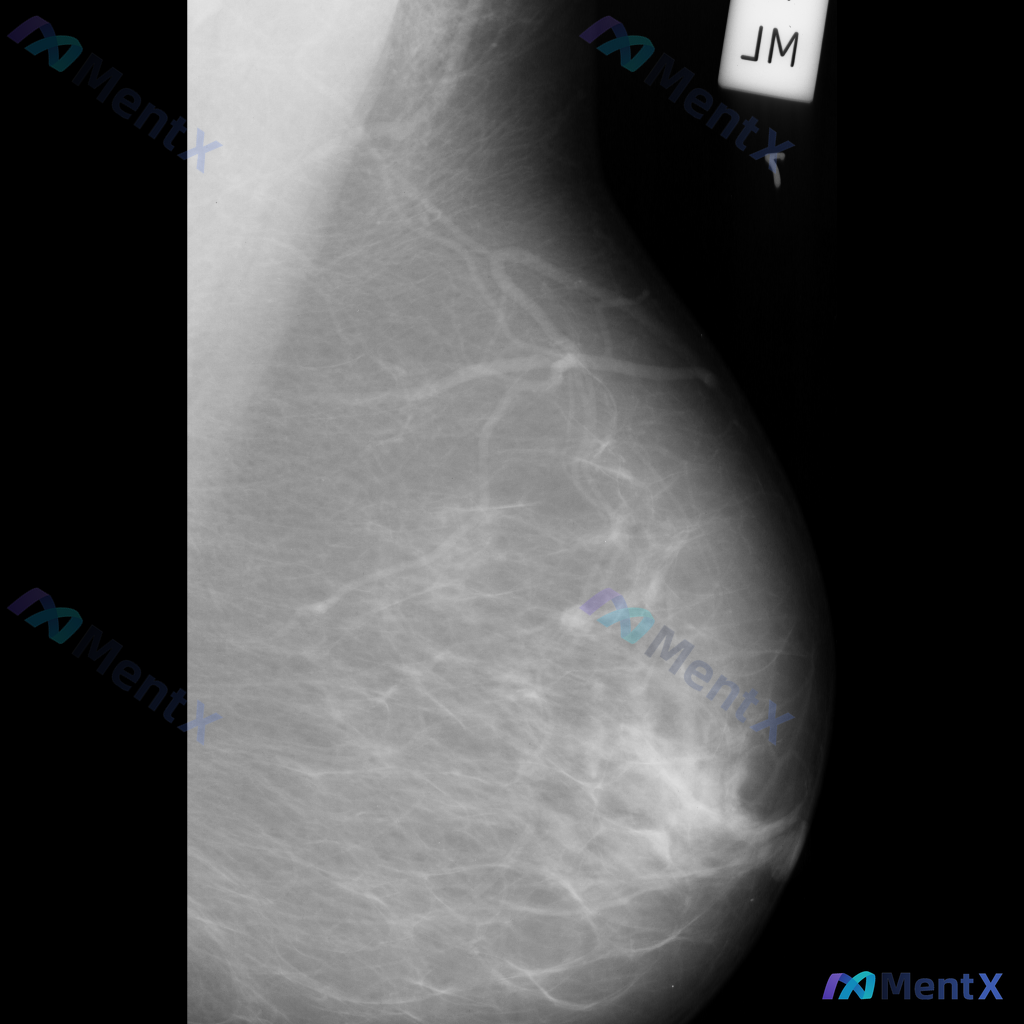

整理到一张左乳内外斜位(MLO)的钼靶影像资料,先和大家讨论一下读片的情况。 目前已知的信息: - 仅提供了左乳的MLO位单张投照影像 - 影像质量基本良好,基本结构可辨 - 后续补充说明提到患者的乳腺构成类型为不均匀致密型(BI-RADS C) 目前暂时没有更多临床病史、对侧乳腺影像或头足位(CC...

整理到一张单张乳腺钼靶的影像资料,大家可以一起看看: 影像里主要能看到这些表现: 1. 乳腺上部区域,沿血管走行分布有线样结构伴条索状和点状钙化; 2. 乳腺实质内部,散在分布着一些粗大斑片状/粗棒状钙化,边缘相对清晰、密度比较高; 3. 乳腺中下部区域,还能看到数个小的、边缘相对清晰的圆形或卵圆形...